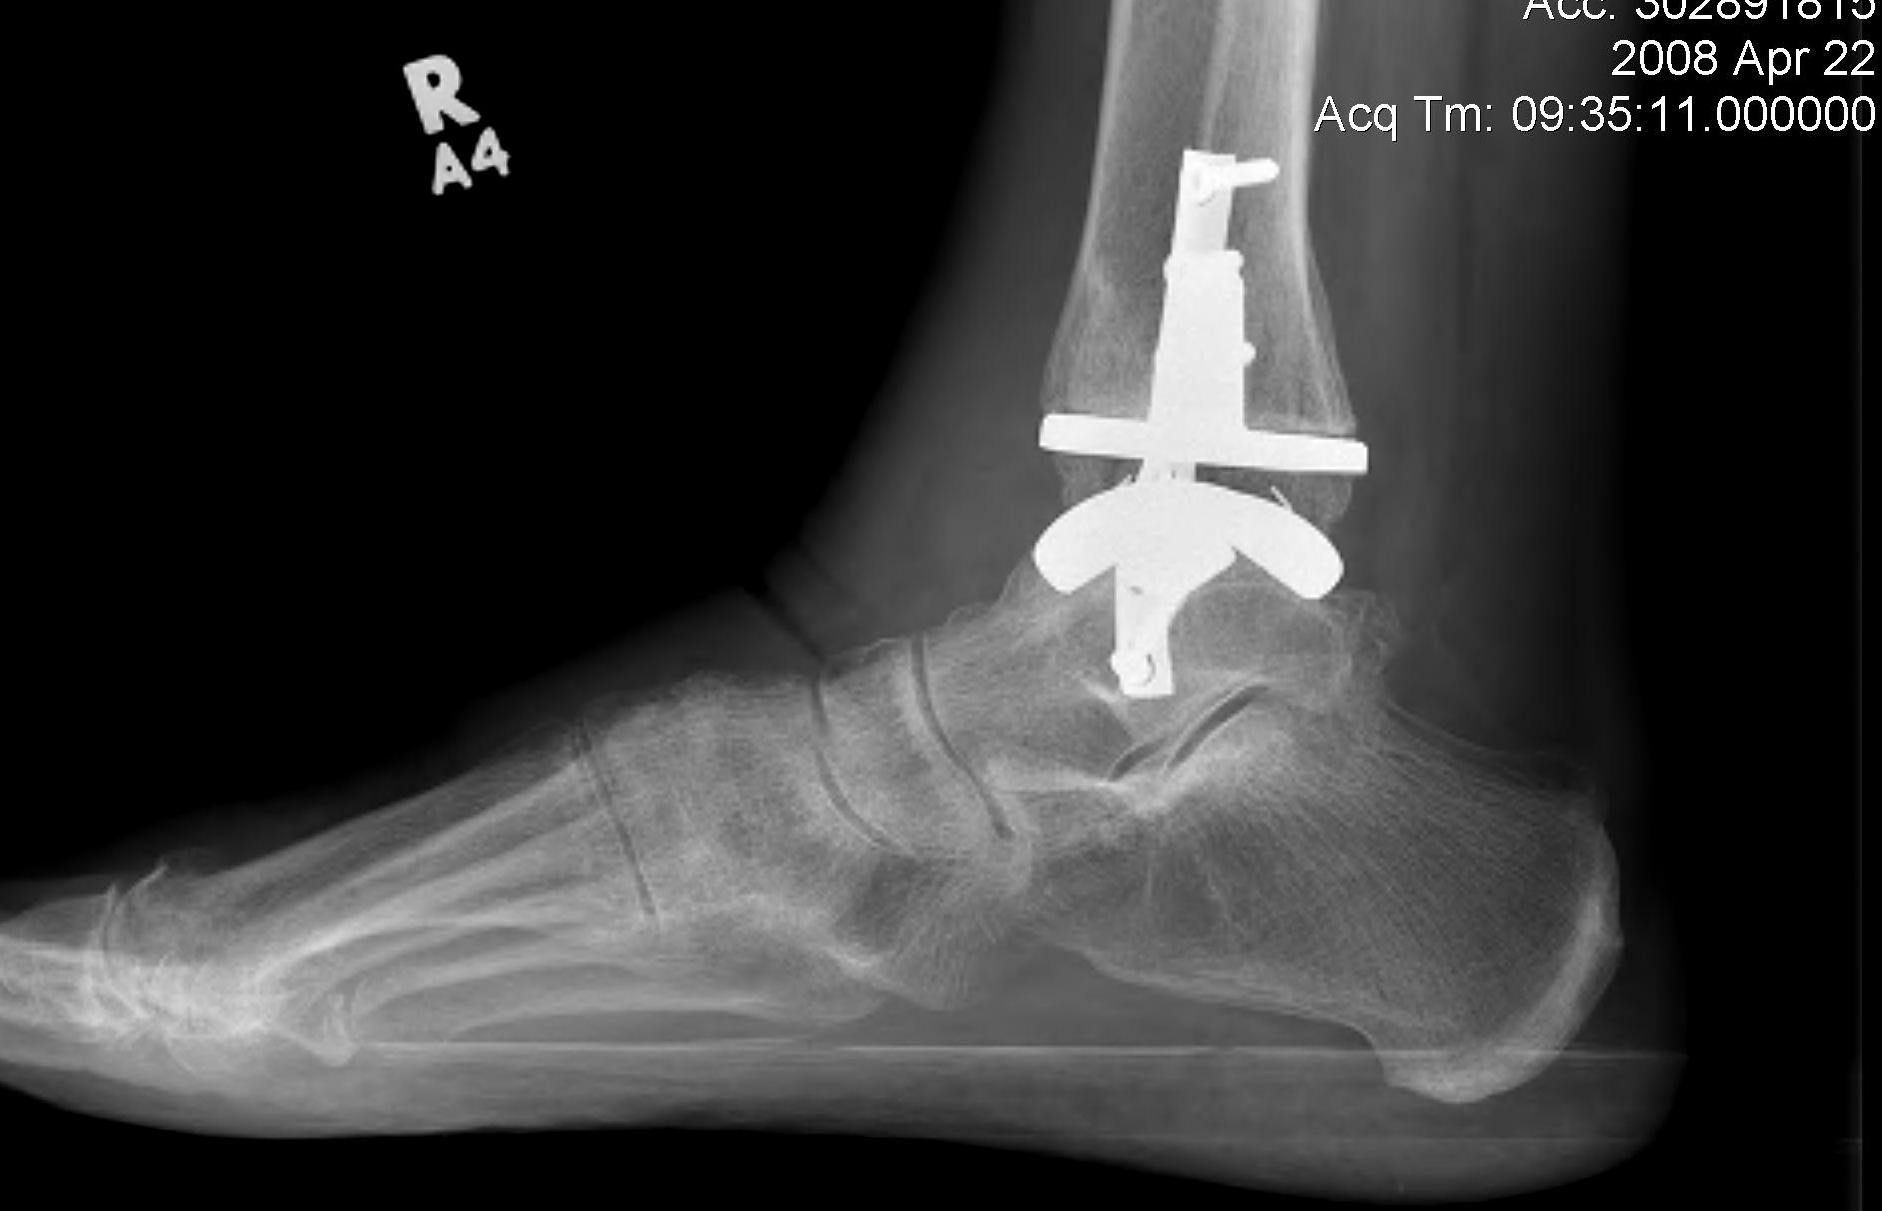

Ankle ArthrodesisResults

90% fusion rates

Non union rates up to 12% Decreased gait speed Poor mobility over uneven surfaces Ankle Arthroplasty

History

First generation (late 70s early 80s)